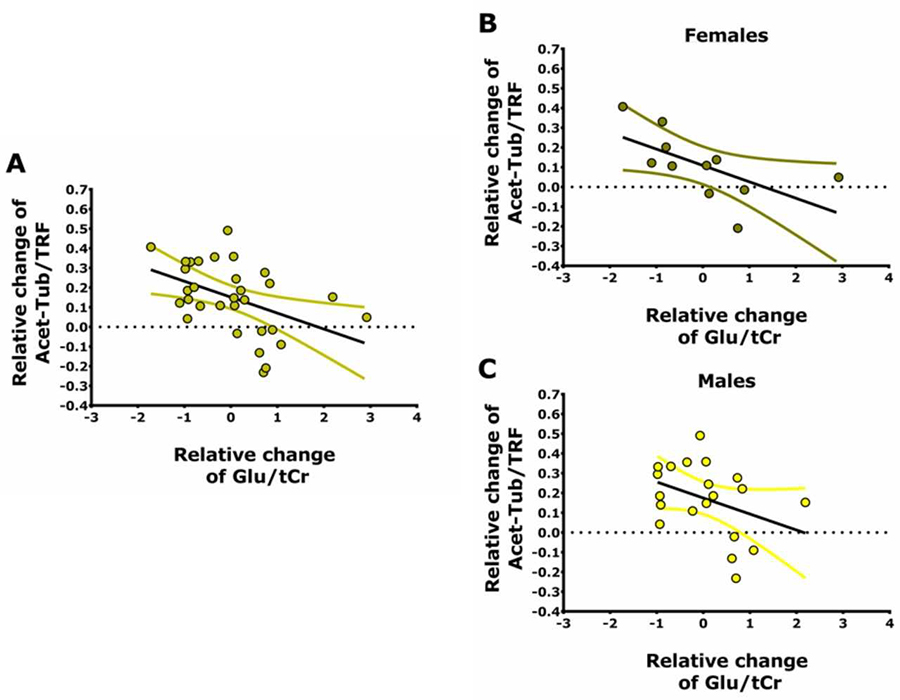

Illustration: Relationship between changes in neurometabolites and blood biomarkers after ketamine infusion in healthy participants.